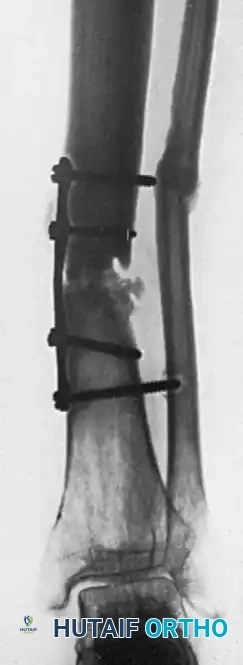

6. Definitive Fixation (The Alternating Screw Technique)

Fixing two unyielding cortical grafts to a mobile nonunion requires a specific, sequential technique to maintain compression and alignment. Fix the two grafts one at a time as follows:

- Provisional Short Screws: Drill and tap through the first graft and the near cortex of the host bone. Fix this first graft to both the proximal and distal host fragments using short temporary screws. This stabilizes the first graft and the host bone as a single unit.

- Definitive Long Screws: Move to the second graft. Drill through the second graft, through both cortices of the intervening host fragments, and into the first graft. Insert fully threaded cortical screws (typically 3.5mm or 4.5mm depending on the bone) that are long enough to pass through all four cortices (Graft 2 -> Host Near Cortex -> Host Far Cortex -> Graft 1).

- Screw Exchange: Once the second graft is secured with long screws, remove the short temporary screws from the first graft. Re-drill these holes through the host bone and into the second graft, and replace them with definitive long screws that pass completely through the entire construct.